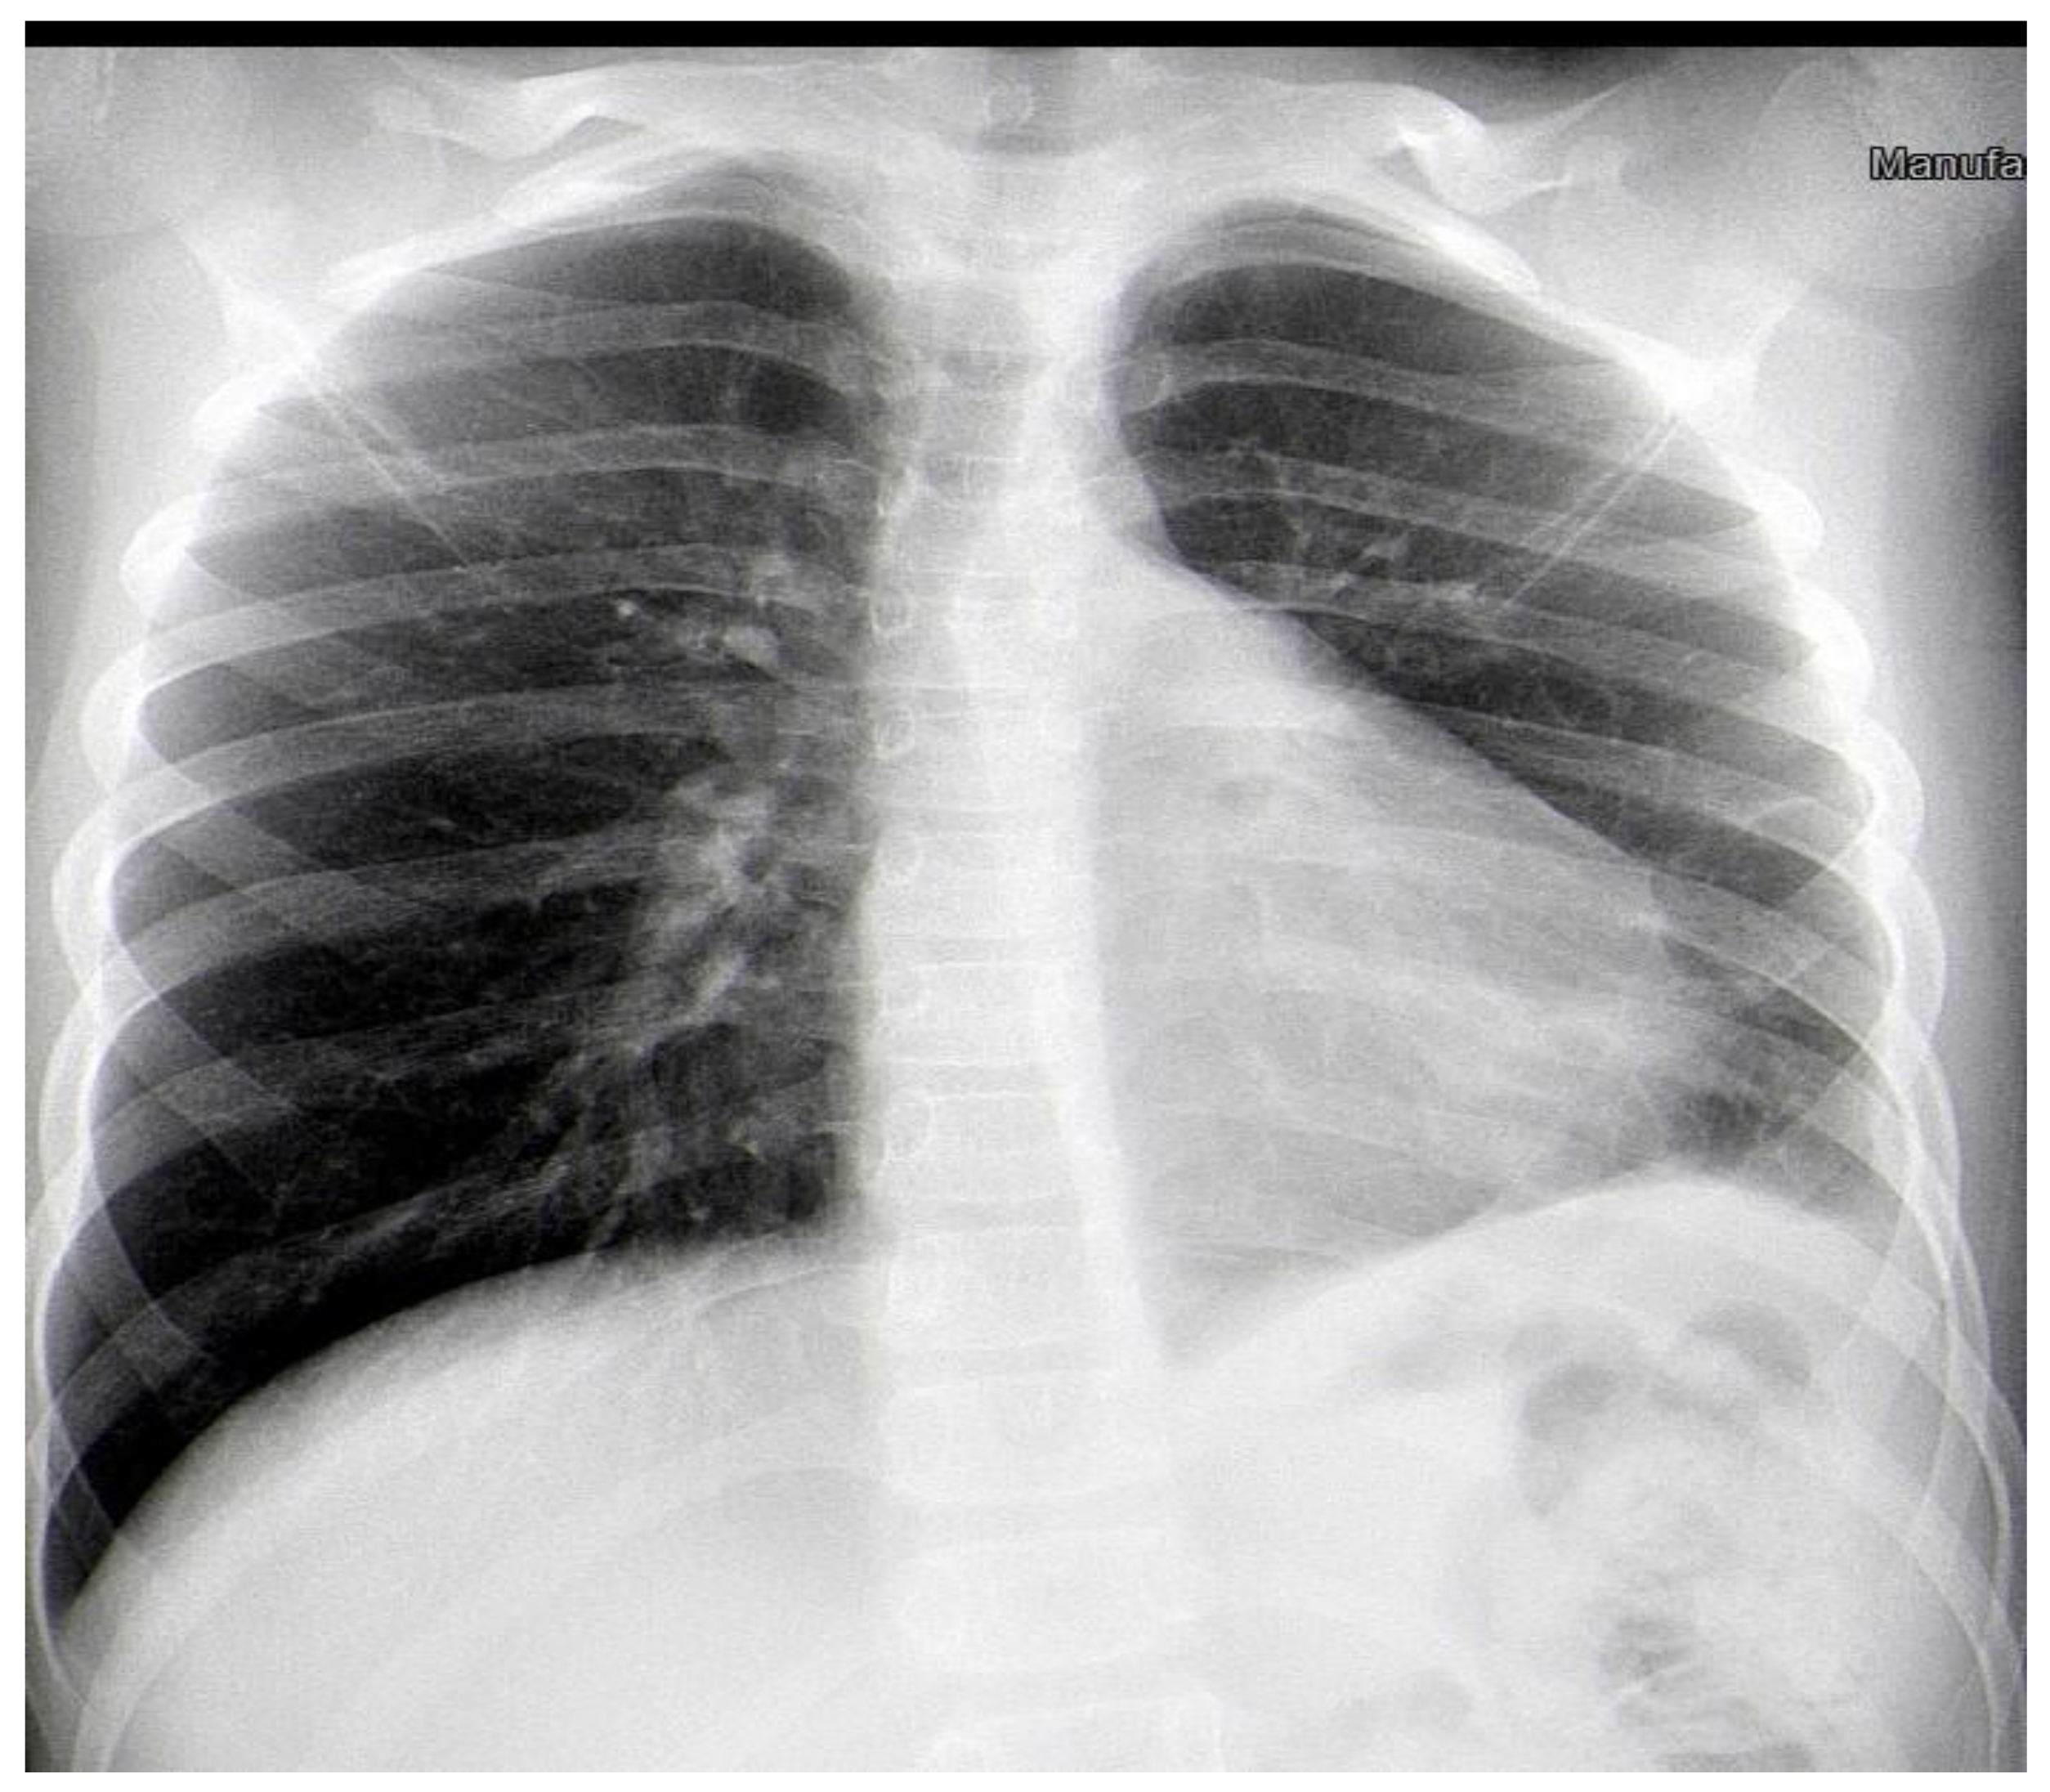

The patient’s complaints persisted, and the child was admitted to the Department of Pediatric Thoracic Surgery for further exams. The condition of the child was stable, with reduced productive cough and reduced vesicular breathing paravertebrally and axillary on the left side of the chest. His hemodynamic was stable, and his abdomen was not tender, without hepatosplenomegaly. Blood and biochemical tests were in the normal range, with slightly increased inflammation markers (leucocytes 11.8 G/L, hemoglobin 137 g/L, hematocrit 0.43 L/L, thrombocytes 404 G/L, CRP 0.59 mg/dL, ASAT 21 U/L, ALAT 13 U/L, creatinine 53 µmol/L). Frontal and chest X-rays revealed atelectasis of the posterior basal segment (Figure 2A,B). A flexible bronchoscopy was performed. The trachea, right main bronchus, and segmental and subsegmental bronchi were without obstruction and pathology. The left main and upper lobe bronchi also were normal. A thick secretion was found in the left lower lobe bronchus, and a bronchoalveolar lavage was performed. Stenosis and obturation resulting from hypergranulation were found in the segmental and subsegmental bronchi of the posterior basal segment (LB10). Recanalization of the LB10 was performed with histopathology and microbiology samples. After five days, a second flexible bronchoscopy was made. Poor improvement was marked by persisting stenosis and obturation of LB10. Again, a biopsy and recanalization with new samples were performed. The microbiology was negative, and the histology showed acute bronchitis. Antibiotics (Ceftriaxone) and symptomatic treatment (Pulmicort inhalations) were extended during the entire hospital stay. The patient was discharged on the 7th day and transferred back to the Department of Pediatric Pulmonology for prolonged treatment.

Figure 2. (A). Frontal chest X-ray—atelectasis of the posterior basal segment. (B). Lateral chest X-ray.